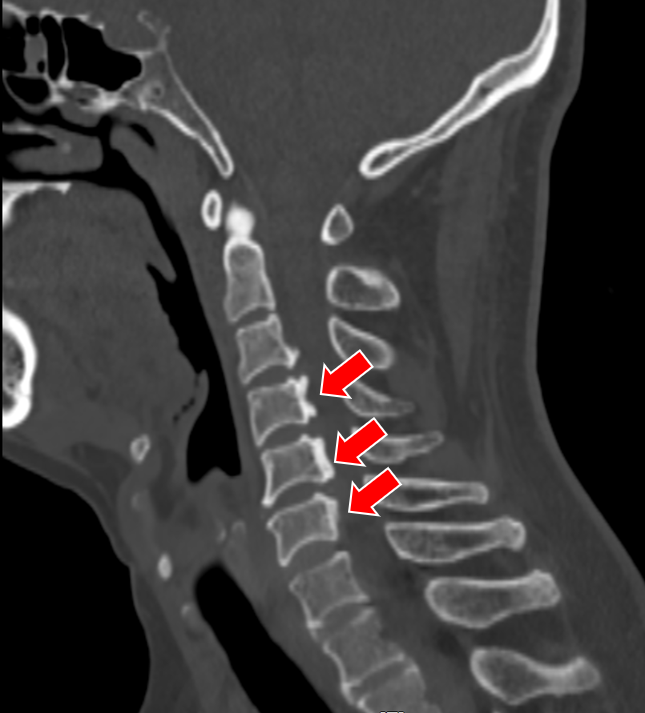

(颈椎CT提示患者C3-6椎体后纵韧带骨化明显,椎管狭窄显著)

无独有偶,我院骨科还为一对姐弟完成了一组颈椎后路手术。姐弟俩吕艳、吕飞(化名)均患有“颈椎后纵韧带骨化症”。弟弟吕飞今年40岁,是位企业白领。别看他年龄不大,其实已多年饱受颈椎病之苦。由于长期伏案工作,这些年他常常感觉自己四肢乏力,走路像踩在棉花上一般,像系纽扣、写字这样的活动也逐渐无法完成,这让他很是着急。通过亲友介绍,他找到姜为民主任寻求帮助,姜主任在仔细的查体和阅片后,判断吕飞的颈椎后纵韧带骨化节段多,症状重,应当尽早手术,解除对脊髓的压迫。